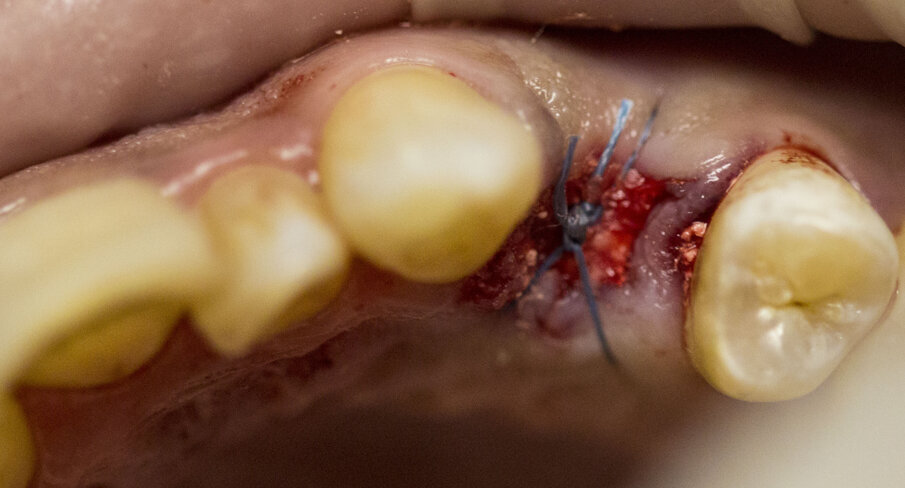

Fig. 3 - Dente fratturato 2.4.

Fig. 4 - Estrazione del dente 2.4.

Fig. 5 - Posizionamento del biomateriale (cono R.T.R., Septodont) nell’alveolo.

Fig. 6 - Biomateriale in situ.

Fig. 7 - Radiografia postoperatoria che mostra il biomateriale in situ.

Fig. 8 - Sutura post-op.

Fig. 9 - Situazione dopo sei giorni.

Fig. 10 - Rimozione della sutura dopo sei giorni.

Fig. 11 - Situazione due settimane dopo: buona guarigione senza interferenze da parte del biomateriale.